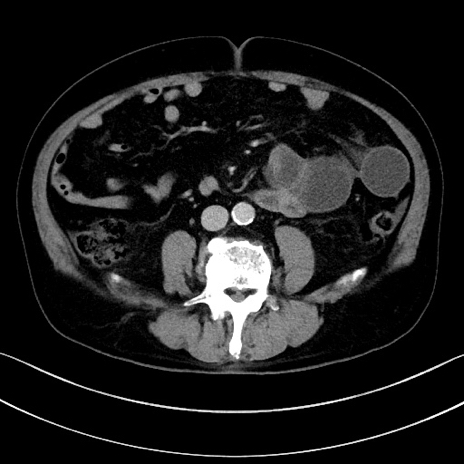

症例15(横断像)

【症例】70歳代男性

【主訴】腹痛

【現病歴】今朝から腹痛あり。全体的に痛い。特に左上の方。排ガスが今日はない。冷や汗が出る。

【既往歴】直腸癌術後

【身体所見】左側腹部〜上腹部に圧痛あり。腹膜刺激症状明らかなではない。軽度反跳痛。左下腹部に術後瘢痕あり。

【データ】WBC 7700、CRP 0.02